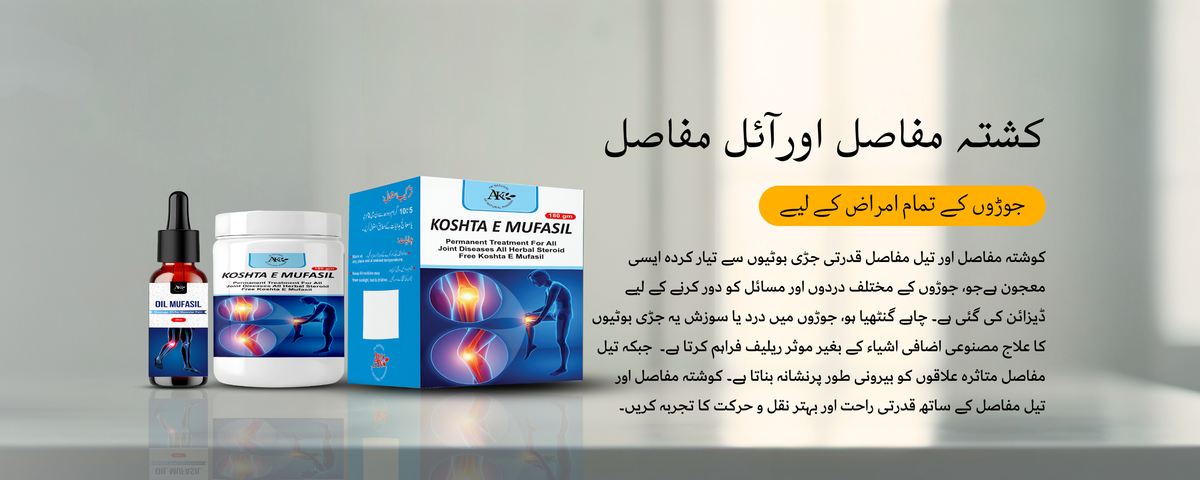

KOSHTA MUFASIL & OIL MUFASIL

میری دادی کو جوڑوں کا درد تھا جس کی وجہ سے ان کو راحت نہیں ملتی تھی۔ کوشتہ مفاصل اور تیل مفاصل نے ان کو بہتر بنایا

جب سے میں نے کوشتہ مفاصل اور تیل مفاسل کا استعمال شروع کیا ہے، میں نے اپنی مشترکہ نقل و حرکت میں غیر معمولی بہتری کا تجربہ کیا ہے۔

How do Koshta Mufasil and Oil Mufasil work?

Koshta Mufasil is an herbal supplement taken orally, while Oil Mufasil is a topical oil applied directly to the affected joints. Both products work synergistically to reduce inflammation, relieve pain, and improve joint mobility.

How quickly can I expect to see results with Koshta Mufasil and Oil Mufasil?

Results may vary depending on individual factors such as the severity of joint pain and overall health. Some users may experience relief within days of starting the regimen, while others may require several weeks of consistent use. Patience and adherence to recommended usage guidelines are key.